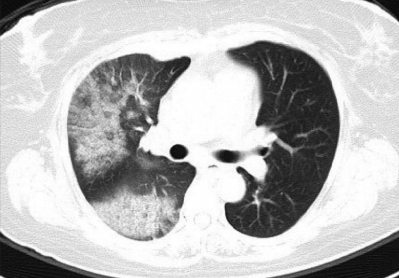

身長 151 cm、体重 70 kg。体温 36.8 ℃。脈拍 92/分、整。血圧 130/102 mmHg。呼吸数 18/分。SpO2 94 %(room air)。呼吸困難の原因は胸水貯留であると考え、入院の上、胸腔穿刺を行い胸水を排液した。呼吸困難は一時的に改善したが、 穿刺1時間後に強い呼吸困難と泡沫状の喀痰がみられ、SpO2 92 %(鼻カニューラ2L/分 酸素投与下)となった。 穿刺2時間後、症状はさらに悪化し、SpO2 85 %(マスク8L/分 酸素投与下)となったため気管挿管を行った。来院時と胸腔穿刺1時間後の胸部エックス線写真と胸部CTとを示す。

胸腔穿刺1時間後